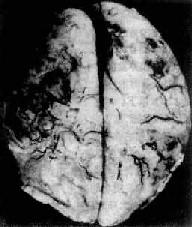

肉眼观,脑脊膜血管高度扩张充血,病变严重的区域,蛛网膜下腔充满灰黄色脓性渗出物,覆盖着脑沟脑回,以致结构模糊不清(图16-10),边缘病变较轻的区域,可见脓性渗出物沿血管分布。在渗出物较少的区域,软脑膜往往略带混浊。脓性渗出物可累及大脑凸面矢状窦附近或脑底部视神经交叉及邻近各池。由于炎性渗出物的阻塞,使脑脊液循环发生障碍,可引起不同程度的脑室扩张。

图16-10 化脓性脑膜炎

蛛网膜下腔内有多量脓液堆积以致大部分脑表面的沟回结构不清;脑膜血管高度扩张充血